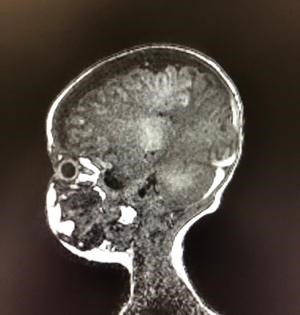

Entre las pruebas de imagen solicitadas, el TAC y RMN craneal evidencian hematomas subdurales crónicos multifocales con sangrado subagudo, trombosis de vena frontal parasagital izquierda y dudosa línea de fractura parietal izquierda. Se realiza fondo de ojo con hemorragias retinianas difusas. La punción lumbar, la RMN de columna y la serie ósea no muestran alteraciones (Fig. 1).

Figura 1. RMN de columna.